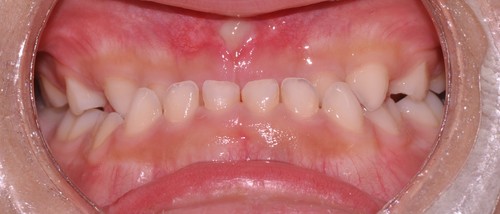

前歯が全体的に受け口になっている症例はもちろんですが、下の写真のように1本だけ反対になっている症例にも効果があります。

↓

4カ月で左前歯の反対咬合が改善されています。さらに歯列の拡大も見られます。